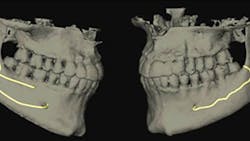

As the inferior alveolar nerve (IAN) approaches the mental foramen, the canal turns upward on the buccal side of the mandible.

The IAN emerges from the mental foramen and generates the mental nerve. The mental portion of the IAC can course straight, vertical, or in an anterior loop fashion. In the anterior loop, the nerve runs upward and courses toward mid-mandible before looping and heading back toward the mental foramen (figure 1).

The literature1 has reported variations in the prevalence of the anterior loop from 7%–88%, with a mean prevalence of around 28%.2 Trauma to this region (mandibular premolar-incisor) can induce sensory disturbances, increased bleeding, and pain post-implant therapy in a region otherwise known as a “safe area.”

A recent review suggested that the traditional thought of staying at least 2 mm away from the IAC should be revisited. This study looked at 60 patients with implants placed within 2 mm of the IAC. The authors noted that even if the dental implant was placed within .75 mm of the IAC, as long as direct transection or compression did not occur, the patient experienced no sensory disturbances.3

Taking a high-quality CBCT image may help with neural imaging and deciphering if an anterior loop is present.